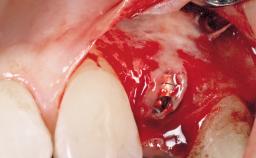

Early Placement of an Implant in a Maxillary Right Central Incisor Site

This 41-year-old female patient was referred to the clinic for the replacement of the right central incisor, since the tooth had developed a root fracture in the long axis that made extraction necessary. The healthy, non-smoking patient was first seen with the tooth still in place. A detailed Esthetic Risk Assessment was performed.The patient was worried about her dental esthetics and had high expectations for a successful treatment outcome from an esthetic point of view. The patient had a medium lip line that displayed parts of the gingiva in the anterior maxilla upon smile.

Bone Augmentation Horizontal|Simultaneous

Augmentation Materials Autogenous chips|Xenogenous|Membrane

Bone Volume Deficient horizontally, allowing simultaneous augumentation